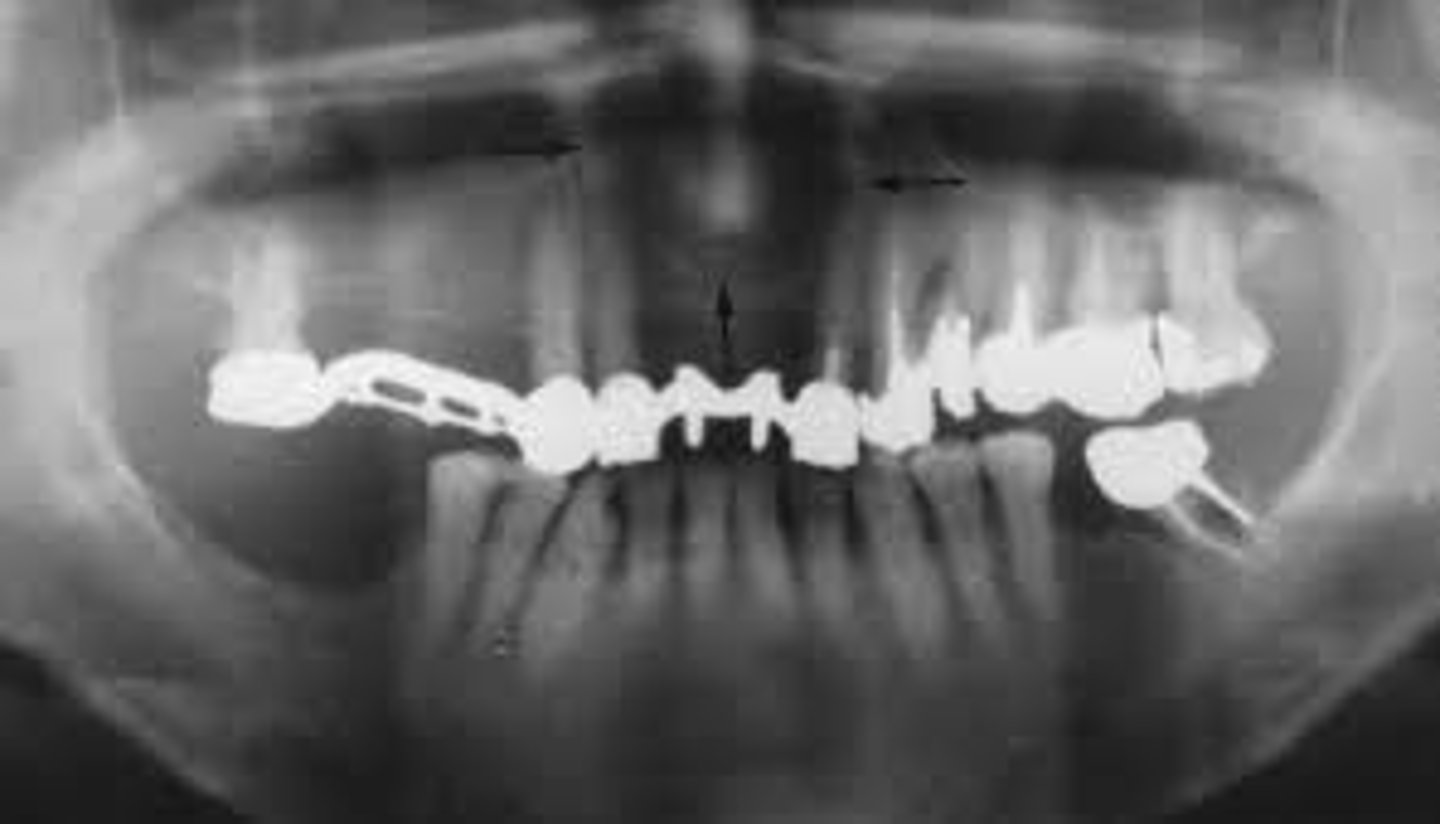

what is this?

what is this radiolucent area in the image?